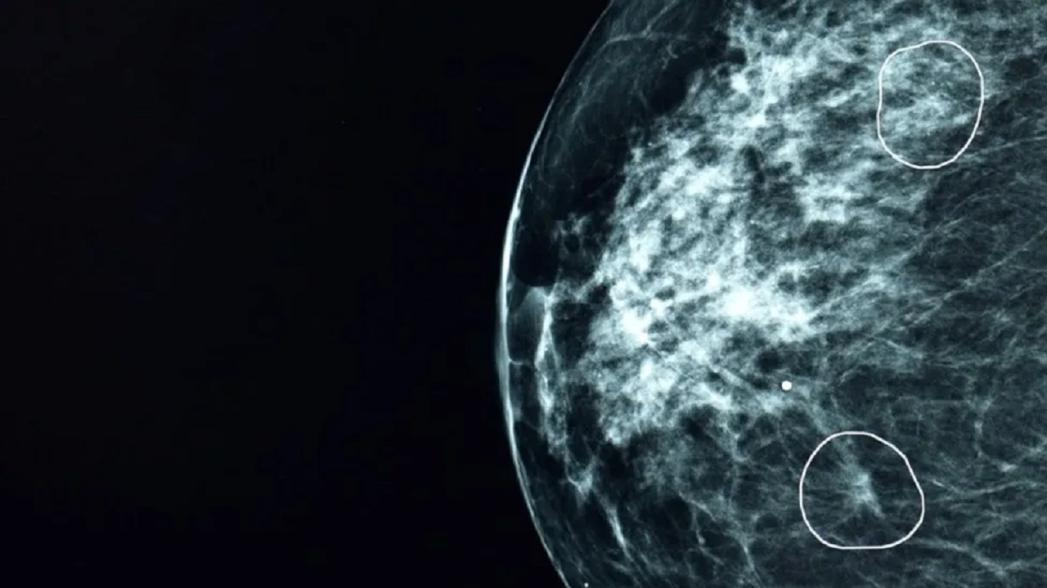

Система на основе искусственного интеллекта (ИИ), протестированная в Национальной службе здравоохранения Великобритании (NHS), успешно выявила крошечные признаки рака груди у 11 женщин, которые были пропущены врачами.

Программа, получившая название Mia, была опробована совместно с врачами NHS и проанализировала маммограммы более 10 000 женщин. Большинство из них не болели раком, но программа успешно выявила всех тех, у кого были симптомы, а также еще 11 женщин, заболевание у которых не выявили врачи.

На самых ранних стадиях рак может быть очень маленьким, и его трудно заметить. Выживаемость пациенток с раком груди, у которых опухоль на момент обнаружения была меньше 15 мм, составляет 90 % в течение последующих пяти лет. Благодаря мгновенной работе такие системы, как Mia, могут сократить время ожидания результатов с 14 дней до трех, утверждает их разработчик компания Kheiron.

Ни один из случаев, участвовавших в исследовании, не был проанализирован только Mia — каждый из них также рассматривался человеком. В настоящее время каждый отдельный снимок рассматривают два рентгенолога, но есть надежда, что в один прекрасный день один из них может быть заменен инструментом, что позволит вдвое снизить нагрузку на каждого из них.